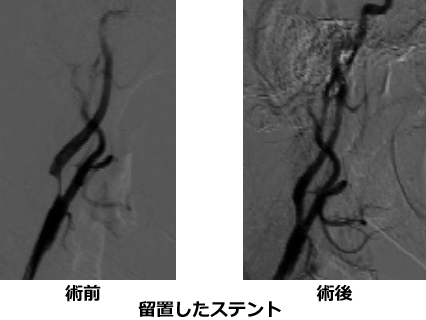

頸動脈ステント留置術 (Carotid Artery Stenting: CAS)

頸部内頸動脈起始部に高度狭窄があると、これにより脳梗塞が生じる恐れがあります。薬物治療が第1選択ですが、狭窄が高度であったりプラークが不安定であったりする場合には、治療に対する危険性を考慮しても、血管拡張術を行った方が脳梗塞発症率が少ないと考えられます。

2) あらかじめ血管拡張用のバルーン(風船)で狭窄部を拡張してステント(血管を広げる金属でできた網)を留置。